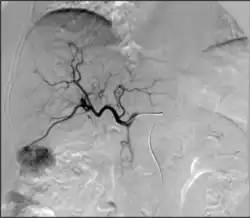

• Chemoembolization: Combined injection of chemotherapy and embolic agents into the arterial blood supply of a tumor, with the goal of both local administration of chemotherapy, slowing "washout" of the chemotherapy drug, and also decreasing tumor arterial supply

• Radioembolization: Combined injection of radioactive glass or plastic beads and embolic agents into the arterial blood supply of a tumor, with the goal of both local administration of radiotherapy, slowing "washout" of the radioactive substance, and also decreasing tumor arterial supply

• Transarterial embolization (TAE)/bland embolization: Injection of embolic material (microparticles, alcohol, glue) through a catheter into the arteries feeding a tumor to completely occlude the tumor's blood supply and cause cell death. The most common indication is for treatment of unresectable liver cancer (hepatocellular carcinoma).[64]

• Transarterial chemoembolization (TACE): Injection of a chemotherapy agent often with microparticles through a catheter into arteries feeding a tumor that both delivers chemotherapy and blocks the blood supply to the tumor to cause cell death[65]

TACE

• Can be performed in different ways:

• Conventional transarterial chemoembolization (cTACE): Injection of lipiodol with high dose chemotherapy with or without microparticles directly into the tumor-feeding arteries.[66]

• Drug eluting bead transarterial chemoembolization (DEB-TACE): delivery of microparticles that are themselves loaded with the chemotherapy agent—typically doxorubicin or irinotecan.

• Selective internal radiation therapy (also known as SIRT or Y-90 radioembolization): Injection of small beads loaded with a radioactive isotope, yittrium-90 (Y-90), into blood vessels feeding a tumor to deliver a lethal dose of radiation to cause cell death.[67] Can be performed in a segmental (radiation segmentectomy) or a lobar (radiation lobectomy) fashion. Radiation lobectomy is commonly performed with the goal of inducing growth of the non-diseased lobe in order to have adequate liver function necessary to undergo surgical resection.